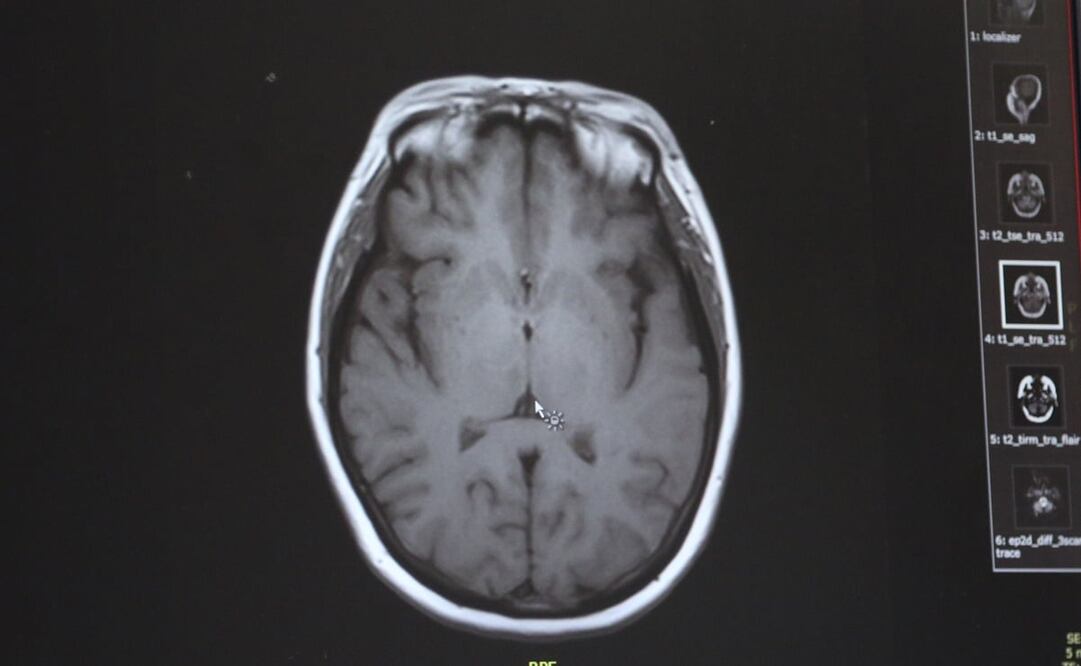

De acuerdo con los CDC, la ameba “comecerebros” suele encontrarse en agua dulce templada, como la de lagos y ríos y aguas termales, y entra al cuerpo a través de la nariz. De ahí sube al cerebro, donde destruye tejido cerebral, una condición conocida como “Primary Amebic Meningoencephalitis” (PAM).

Entre 1962 y 2018, señalan los centros, 145 se infectaron con la ameba y sólo cuatro sobrevivieron. Los CDC sostienen que las personas no se pueden infectar con la ameba bebiendo agua contaminada. En cambió, sí se pueden hacerlo cuando el agua les entra por la nariz, ya sea por sumergir la cabeza o limpiarse la nariz con el líquido contaminado, algo que puede ocurrir en prácticas religiosas.